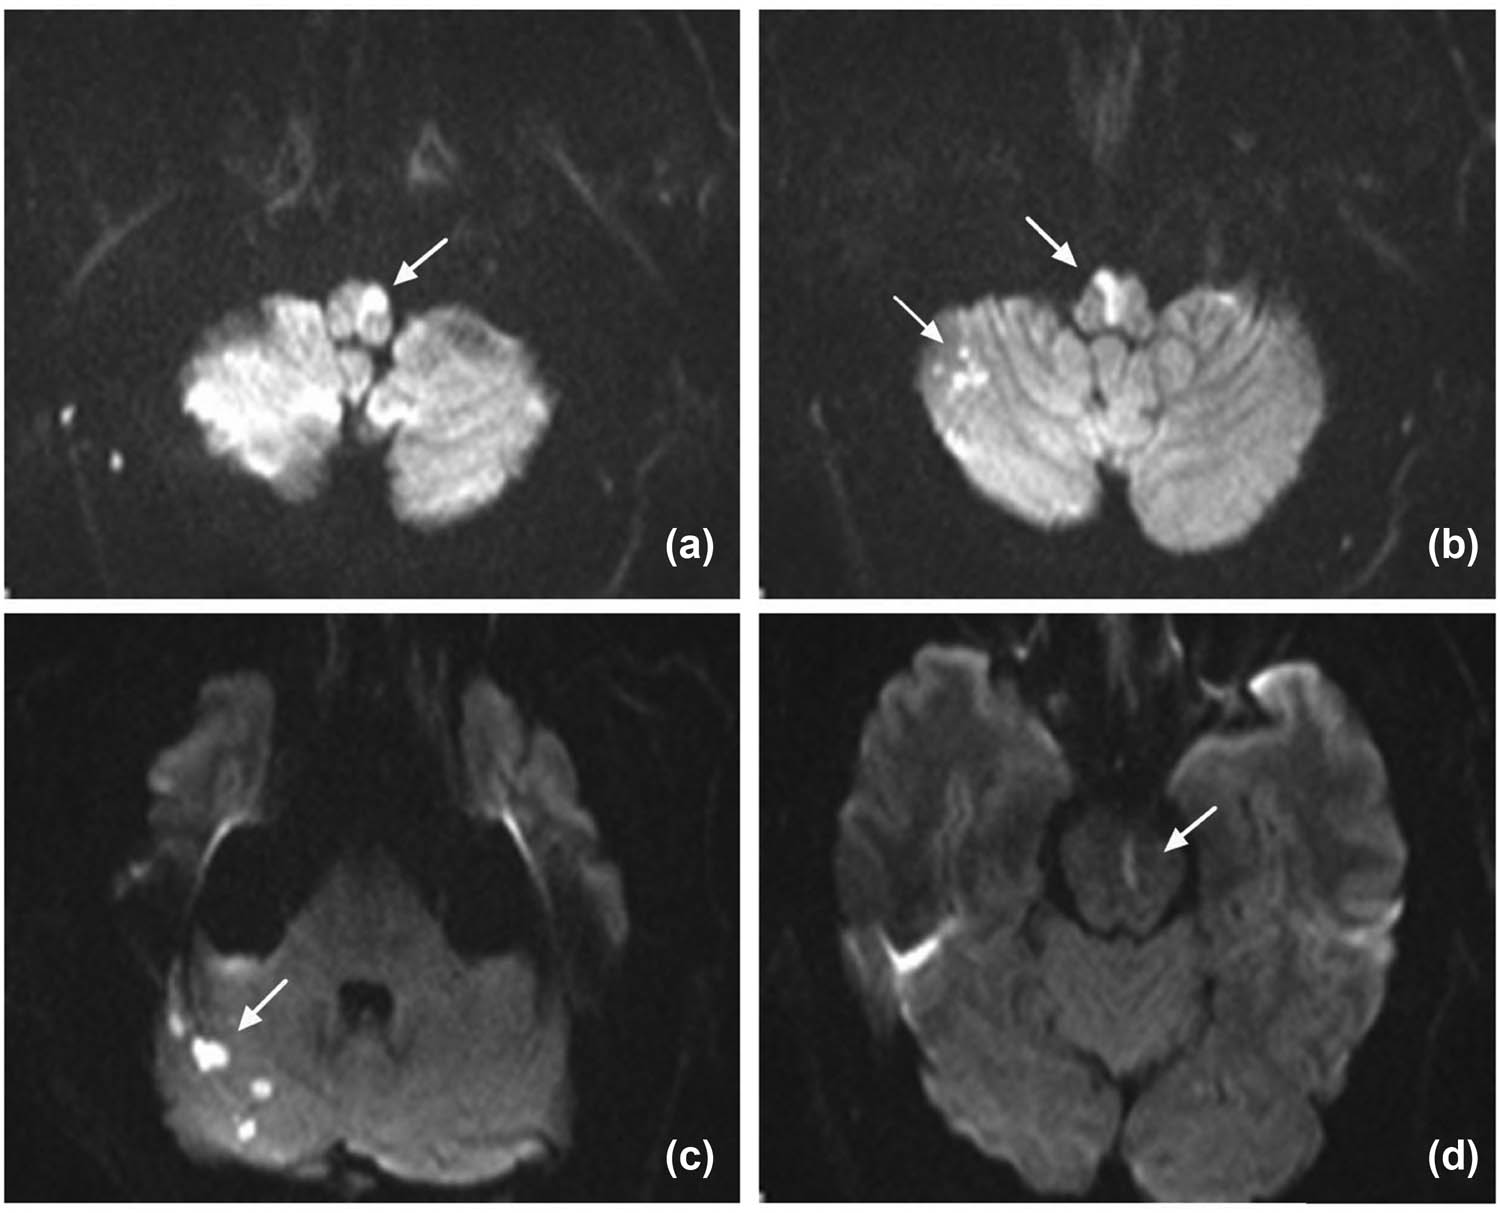

The initial brain MRI was performed 10 h after the onset of the symptoms. The consecutive horizontal sections were noted on diffusion-weighted MRI at 3.0T, a defined hyperintensive linear signal at right anterior-medial territory with a dot-like signal on the other side, which disclosed an atypical “heart-shaped” hyperintensity in the medial medulla (Figure 1a and b). In addition to the medulla oblongata, the infarcted areas also included pons and the right cerebellar hemisphere. Axial T2-weighted MRI image showed hyperintensive signal, while apparent diffusion coefficient (ADC) image (axial) showed hypointensity in the same region. Meanwhile, the signals remained normal on fluid-attenuated inversion recovery (FLAIR).

(Axial DWI imaging): (a and b; arrow) bilateral medial medullary infarction involves the ventral, middle parts of the medulla oblongata, which were compatible with atypical “heart appearance.” (b and c) The right cerebellar hemisphere and (d) pons also showed high-intensity lesions.